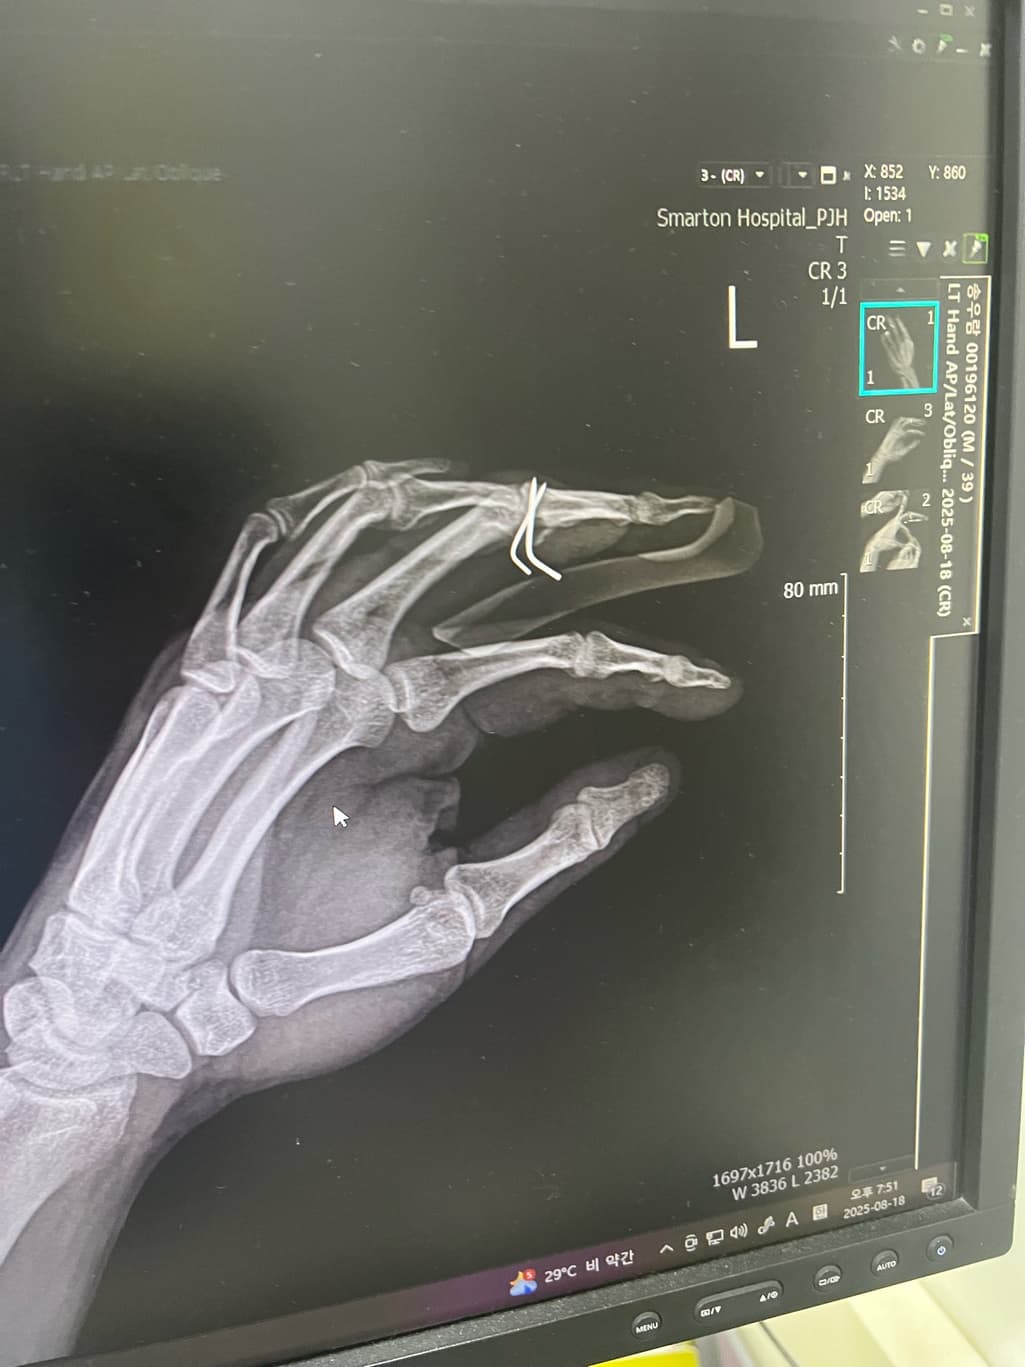

올려주신 엑스레이와 ct를 보면 손가락 뼈에 핀이 삽입되어 고정된 상태입니다. 핀은 뼈가 충분히 붙을 때까지 제거하지 않는 것이 안전하고 수술 후 5일 정도는 아직 뼈가 완전히 안정되지 않은 초기 상태입니다.